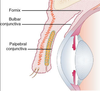

Describe the location of the lacrimal fossa

Formed by the frontal process of the maxilla and the lacrimal bone

Below is continuous with the bony nasolacrimal canal which extends into the inferior meatus (beneath inferior turbinate)